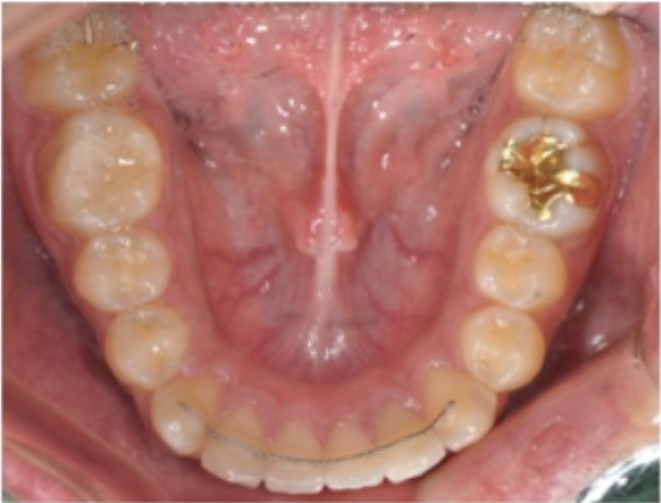

진료를 하다 보면 교정이 잘 끝났는데도 유지 관리가 소홀해 재발이 되어 오시는 분들을 종종 뵙습니다. 특히 해외 유학이나 군 복무 등으로 장기간 치과를 오지 못하다가, 유지장치가 떨어졌는데도 방치하여 치아 사이가 벌어져서 오시는 경우를 보면 참 안타깝습니다. 오늘은 교정전문의로서 유지장치가 왜 중요한지, 비용은 대략 어느 정도인지, 그리고 떨어졌을 때 어떻게 대처해야 하는지 정리해 드리겠습니다. 1. 왜 유지장치가 필요한가? (회귀 현상의 이해) 교정은 물리적인 힘을 가해 치아를 이동시키는 과정이고, 유지장치는 그 결과를 ‘굳히는’ 장치입니다. 교정 직후의 치아는 보기에는 가지런해 보이지만, 치아 뿌리를 감싸고 있는 잇몸 조직은 아직 말랑말랑하고 불안정한 상태입니다. 고무줄을 당겼다 놓으면 원래대로 돌아가려는 성질이 있듯이, 치아도 원래 있던 자리로 돌아가려는 회귀 성향(Relapse)이 매우 강합니다. 연구에 따르면 교정 장치 제거 후 초기 6개월이 치아가 틀어지려는 힘이 가장 강한 시기입니다. 이 시기를 잘 넘겨야 비로소 평생 가는 가지런한 치열을 가질 수 있습니다. 유지장치는 크게 고정식과 가철식으로 나뉩니다.

고정식 유지장치는 치아 안쪽에 가느다란 철사를 붙여 24시간 잡아주는 방식이고 (심미적이지만 탈락 주의),

가철식 유지장치는 탈착이 가능한 투명 장치나 철사 장치로 관리가 편하지만 착용 시간을 안 지키면 효과가 없습니다. 2. 교정 유지장치 비용, 왜 차이가 날까요? 이미인교정치과의 대략적인 유지장치 관련 비용은 다음과 같습니다. (※ 환자분의 구강 상태와 병원 이벤트 정책에 따라 변동될 수 있으니, 정확한 비용은 내원 상담을 부탁드립니다.) 유지장치 전체 제작 : 약 60만 원 선 (본원 프로모션 적용 시 변동 가능) 가철식 유지장치(리테이너) 재제작 : 개당 15만 원 ~ 20만 원 선 고정식 유지장치 재부착 : 부위당 3만 원 ~ 10만 원 선 비용 차이는 사용하는 재료, 환자의 치열 상태(난이도), 유지 관리 기간 등에 따라 달라집니다. 특히 유지장치가 자주 탈락하거나 변형이 오면 추가 비용이 계속 발생할 수 있으므로 관리가 무엇보다 중요합니다. 3. 유지장치가 떨어졌을 때! 절대 해서는 안 되는 행동! 가끔 이렇게 묻는 분들이 계십니다. "철사가 살짝 떴는데, 안 불편하니까 그냥 다음에 가도 되죠?" 아니요, 절대 방치하시면 안 됩니다! 고정식 유지장치의 접착제(레진)가 일부 떨어지면, 그 틈으로 치아가 미세하게 움직이기 시작합니다. 우리 눈에는 안 보이지만 치아는 계속 원래 자리로 돌아가려고 힘을 쓰고 있기 때문이죠. 4. 유지장치 수리 및 재부착 과정 치과에 오시면 과정은 생각보다 간단합니다. 보통 20~30분 내외로 진행됩니다. 검진 및 평가: 떨어진 부위를 확인하고, 그사이 치아가 움직이지 않았는지 체크합니다. 기존 접착제 제거: 치아 표면에 남아있는 거친 접착제를 깨끗이 다듬습니다. (스케일링과 비슷합니다.) 재부착: 치아를 건조한 뒤 새 레진으로 유지장치를 다시 단단하게 고정합니다. 이 과정은 통증이 거의 없으니, 겁먹지 말고 빨리 오시는 게 비용과 시간을 아끼는 지름길입니다. 5. 유지장치 관리는 ‘생활 루틴’이 되어야 한다 한번의 유지장치 탈락이나, 무심코 씹은 얼음이나 딱딱한 음식이 공들여 쌓은 교정 결과를 무너뜨릴 수 있습니다. 그래서 저는 항상 환자분들께 이렇게 말씀드립니다. “교정 치료는 1~2년이지만, 유지 관리는 평생입니다.”